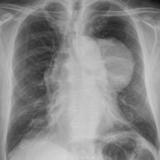

Case 9 Thymoma PA

Date: 04/04/2010

Views: 3252